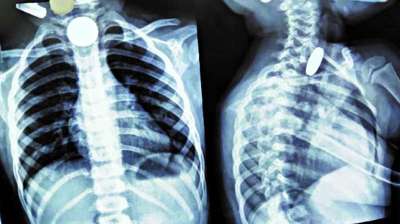

खिलौना नहीं सिक्का था! बच्चे ने निगले 5-10 रुपये के सिक्के, डॉक्टरों ने ऑपरेशन कर निकाले

दिल्ली : दिल्ली के एक सरकारी अस्पताल के डॉक्टरों ने 12 वर्षीय बच्चे की जान बचाई है। बच्चे ने पांच और दस रुपये के तीन सिक्के निगल लिए थे। सिक्के...